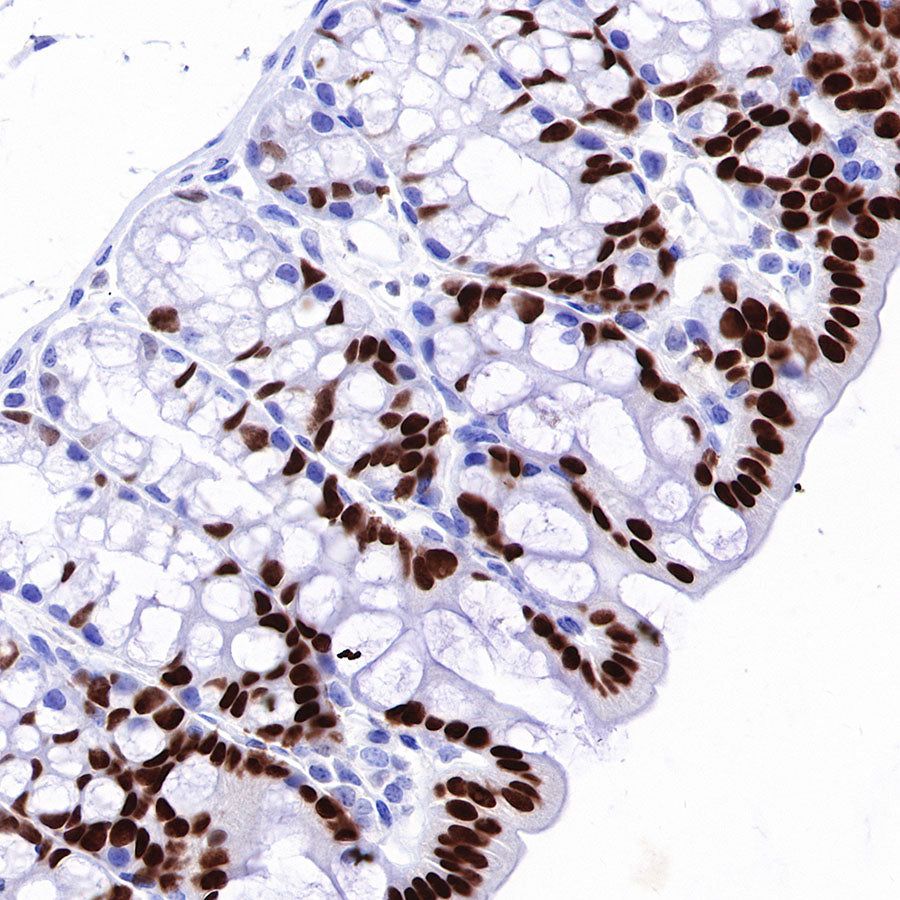

Immunohistochemistry

IHC shows positive staining in paraffin-embedded human colon. Anti-HNF4α antibody was used at 1/500 dilution, followed by a HRP Polymer for Mouse & Rabbit IgG (ready to use). Counterstained with hematoxylin. Heat mediated antigen retrieval with Tris/EDTA buffer pH9.0 was performed before commencing with IHC staining protocol.

IHC shows positive staining in paraffin-embedded human colon cancer. Anti-HNF4α antibody was used at 1/500 dilution, followed by a HRP Polymer for Mouse & Rabbit IgG (ready to use). Counterstained with hematoxylin. Heat mediated antigen retrieval with Tris/EDTA buffer pH9.0 was performed before commencing with IHC staining protocol.